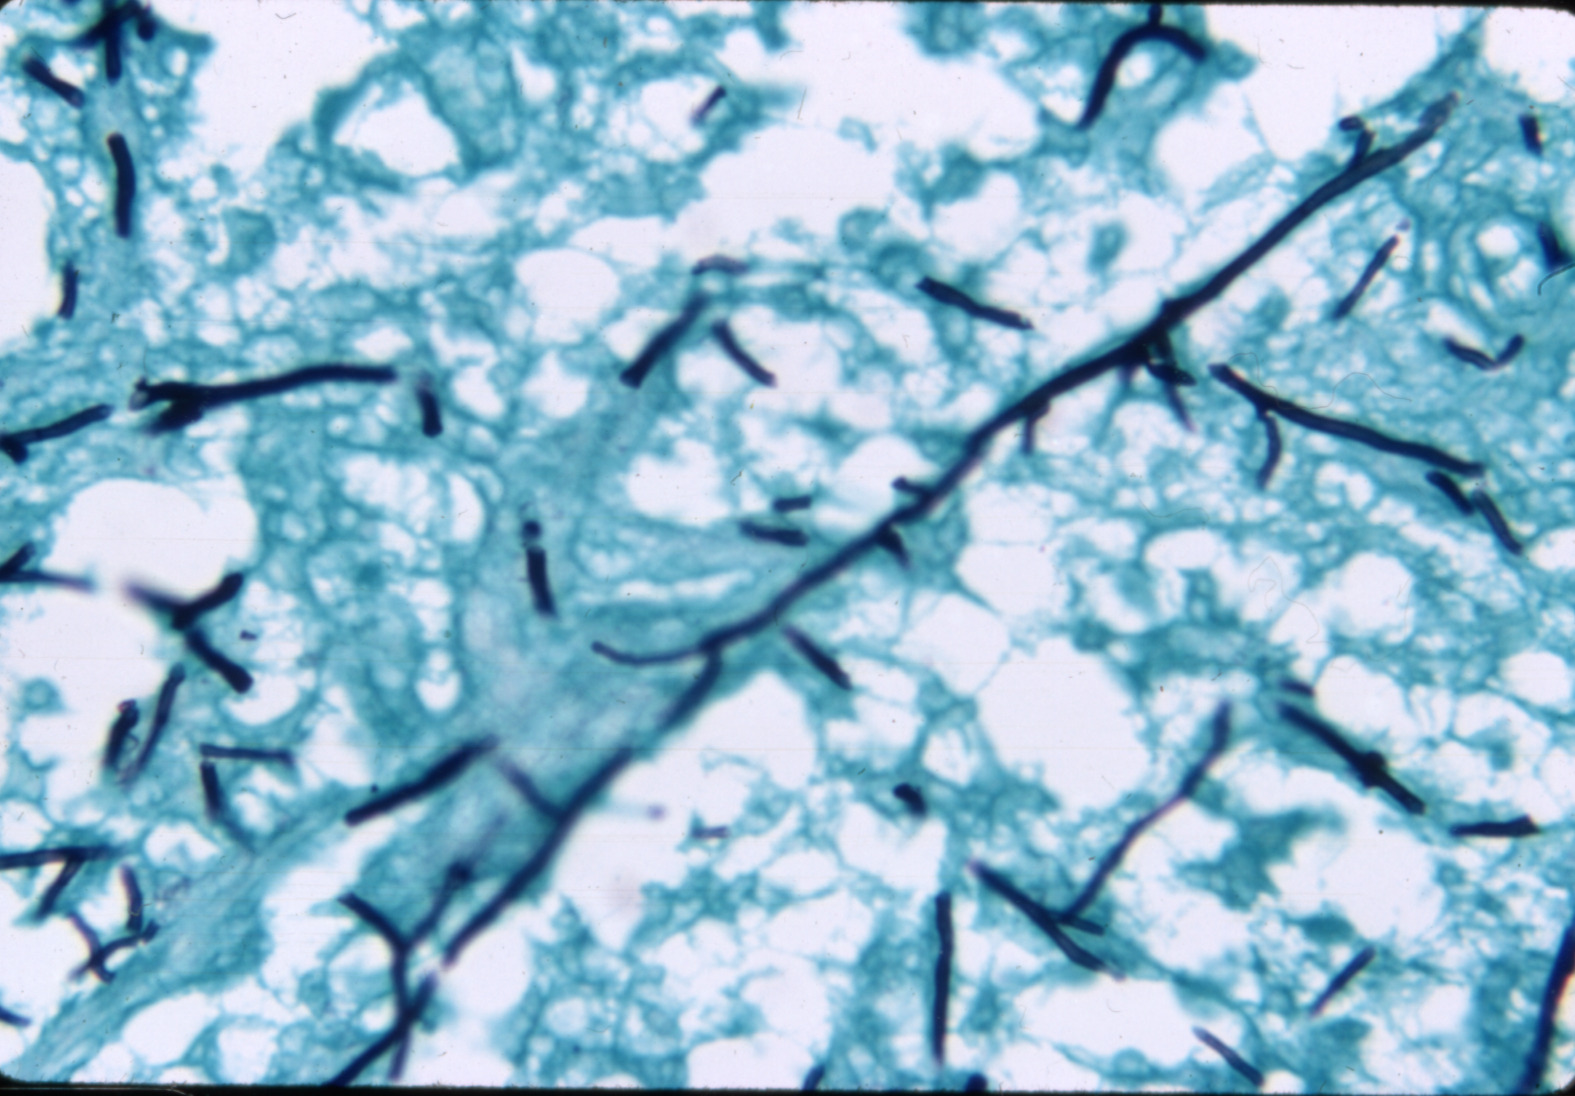

Aspergillosis-dactylariosis (slide study set no. 9)

Poultry--Diseases Aspergillosis

Slide Study Set #9, Aspergillosis-Dactylariosis (includes 24 color slides), 1978